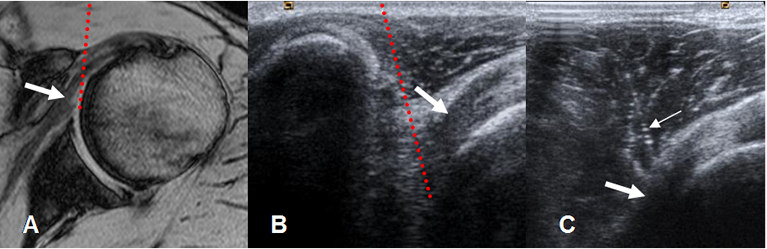

La artroresonancia (ArtroRM) es la mejor técnica para evaluar los ligamentos y el labrum glenoideo. (Fig 23 a 26). La aplicación de la mezcla intra-articular del contraste, puede hacerse mediante guía fluoroscópica o ecográfica. (13). La ecografía se considera la técnica mas fácil, rápida y menos dolorosa. (13). (Fig 22).

Fig 22. Técnica de ArtroRM por ecografía.

A: RM axial en FFE y B: Ecografía vista axial. Abordaje anterior, con trayecto de la aguja en el espacio coracohumeral. Al atravesar el subescapular (Flechas gruesas), se inyecta el contraste.

C: Ecografía axial. Aguja (Flecha delgada) cruzando el músculo subescapular. (Flecha gruesa).